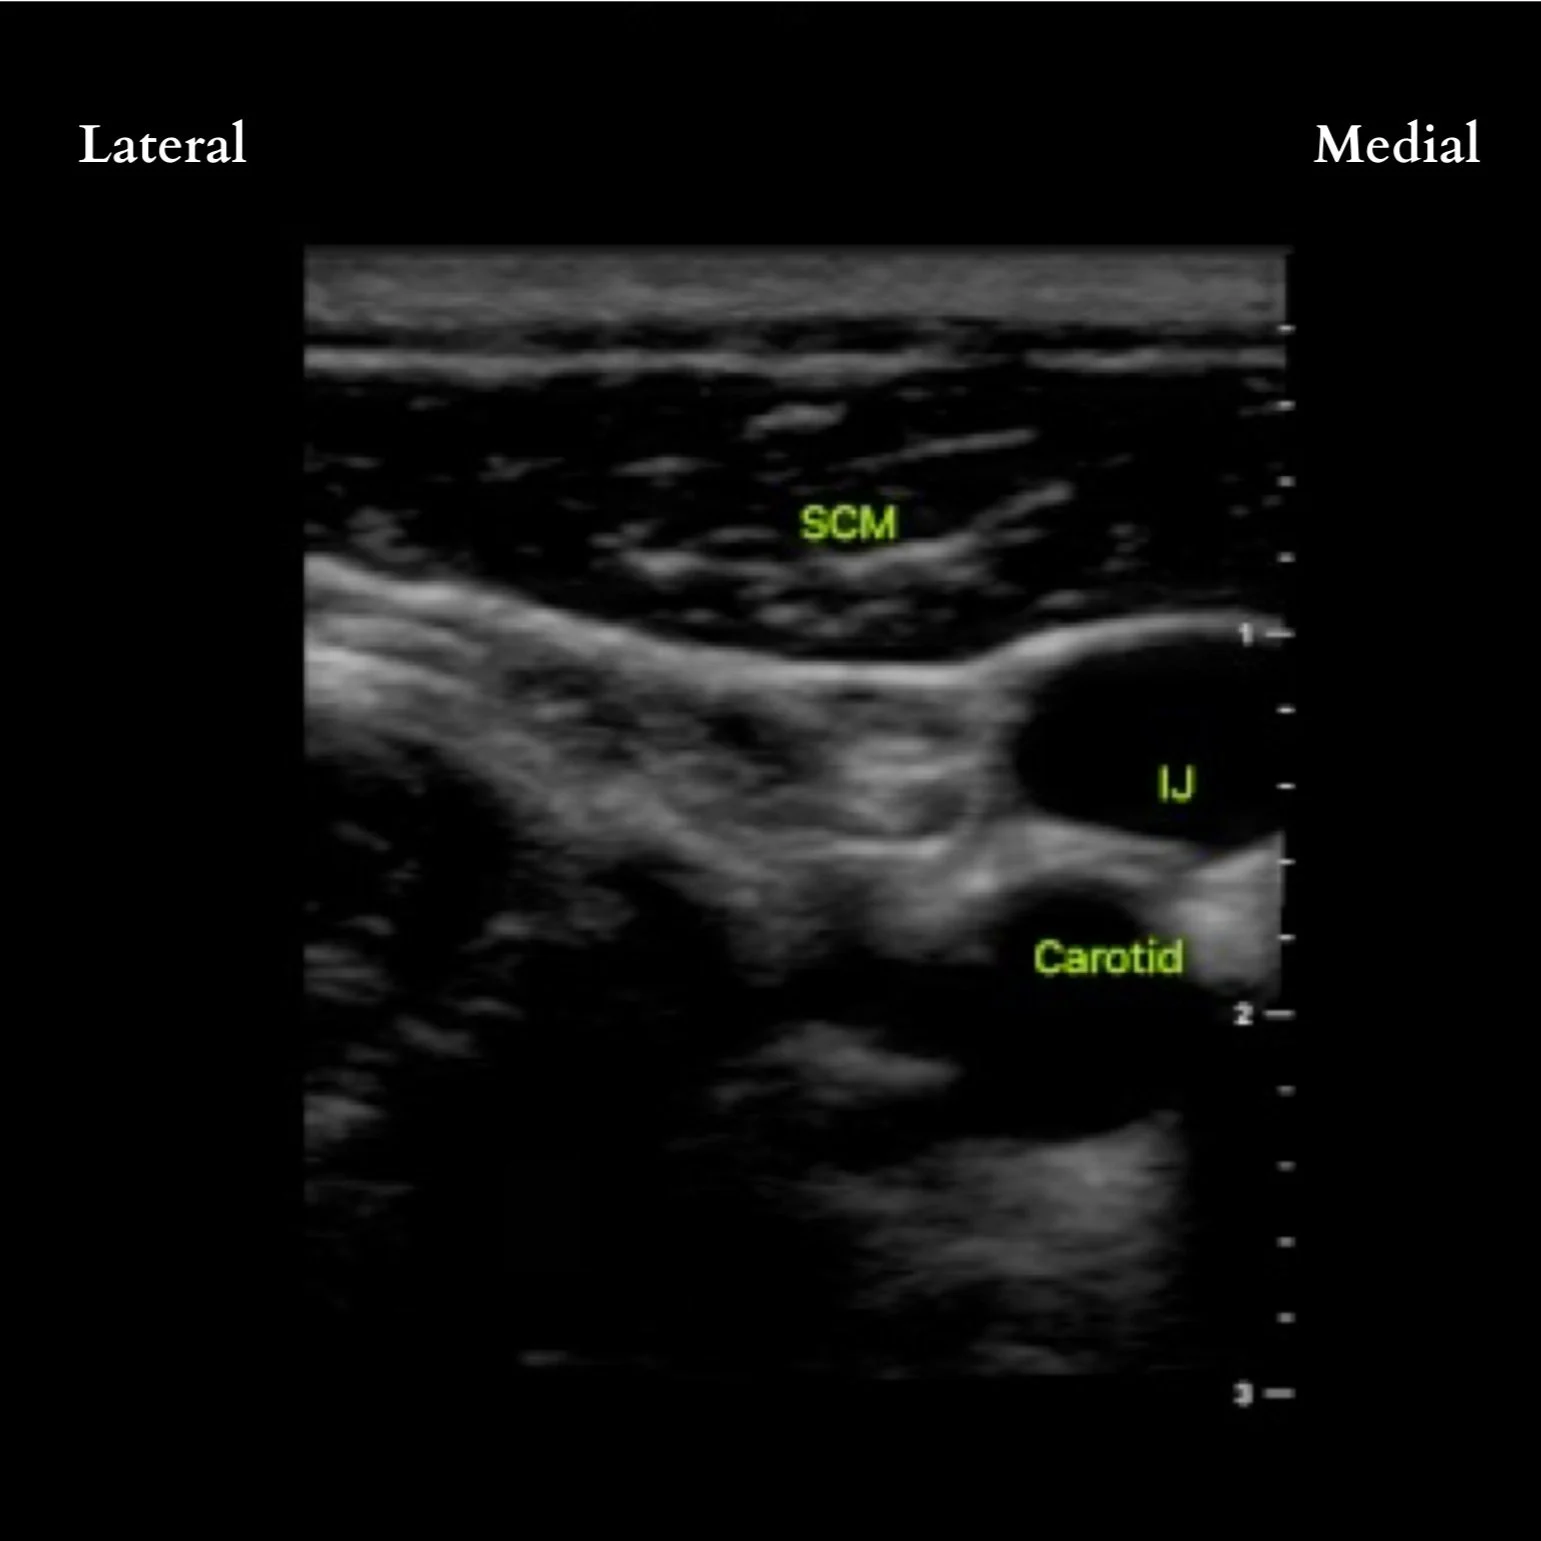

After sterile prep, place probe on the ipsilateral neck at level of cricoid cartilage (C6, roughly the middle of the SCM muscle)

Moving the probe from medial to lateral, trace the SCM as it tapers laterally. If having trouble, first locate the great vessels. The SCM lies anteriorly.

If possible, identify the cervical plexus deep and posterolateral to the lateral edge of the SCM muscle as a hypoechoic collection of nodules. If not identifiable, LA can be deposited beneath the lateral edge of the SCM and prevertebral fascia. If in the correct plane, the LA will 'unzip' the layers similar to a TAP or rectus sheath block. Adjust needle tip accordingly to achieve this view. The phrenic nerve is routinely in this fascial plane (though deeper and medial), so ensure LA spread is more lateral and superficial to avoid unintentional phrenic nerve block.